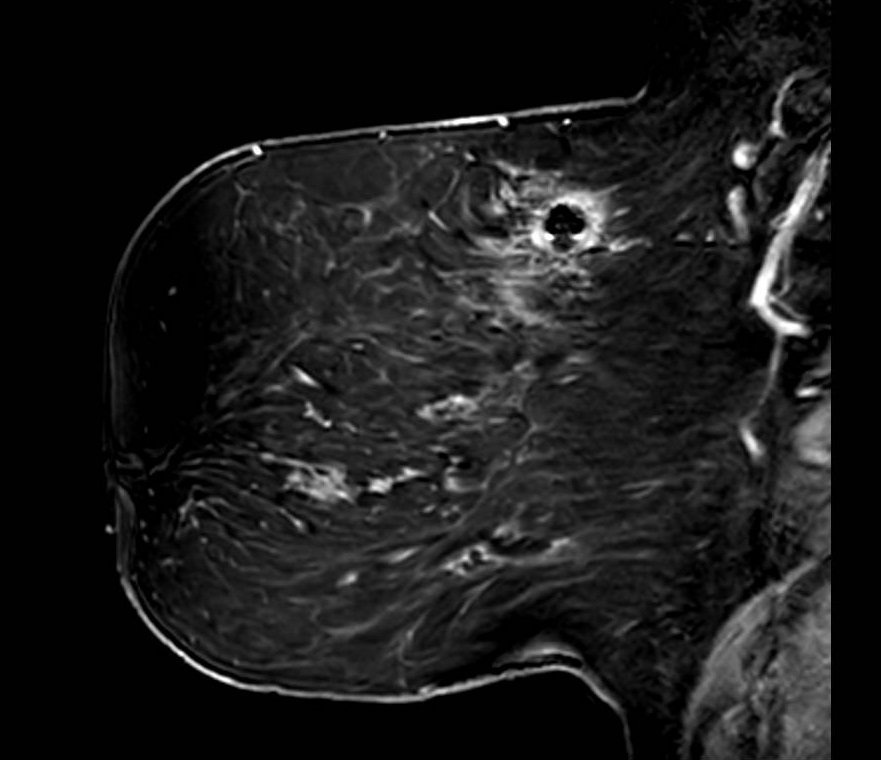

Fat Sat / B0 - Port

Unilateral fat suppression failure secondary to port-o-cath. Axial fat-saturated T1-weighted image demonstrates failure of fat suppression in the right breast with preserved suppression on the left. In addition to the focal signal dropout at the port site, the opposite side of the right breast demonstrates diffuse high signal intensity (bright fat), reflecting regional off-resonance that shifts fat signal outside the suppression bandwidth. This pattern indicates a broader ipsilateral B0 perturbation rather than an isolated focal device effect.